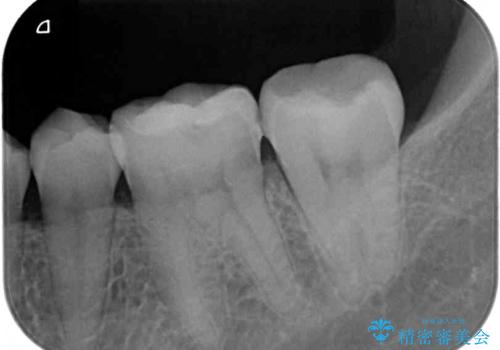

- 左右下顎の奥歯に違和感を感じるとのことで来院された患者様です。

最近ものが挟まりやすくなったり、冷たいものがしみるようになったりと言った症状があり、診査したところ、歯質の欠損や不適修復物などが認められました。

精度の高いセラミックインレーによる修復治療が第一選択となりますが、一方の歯は元々修復物が大きく、咬合力の強い方であったので、セラミッククラウンによる補綴治療を行うこととしました。